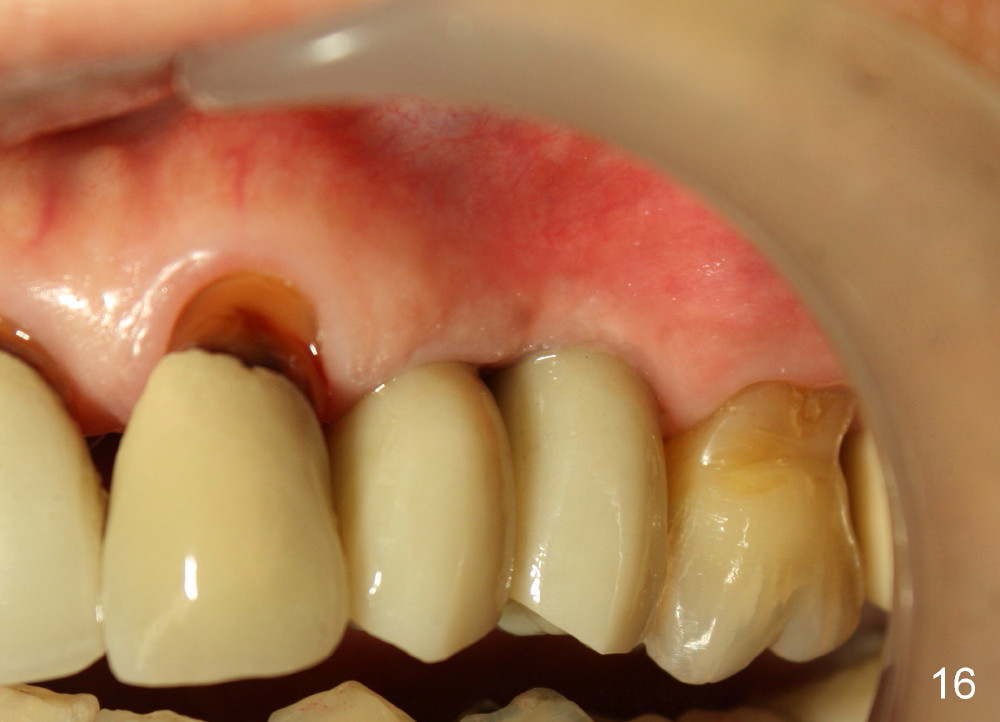

Three month follow-up shows that the gingiva and bone heal around these two implants (Fig.13-15).  Crowns are cemented 4.5 months postop (Fig.16).  There is no or minimal bone loss 9 months post cementation (Fig.17, as compared to Fig.15).  The bone is stable around the implants 18 months post cementation (Fig.18 panoramus).  Root canal therapy is done at #14 between the last follow up appointments.